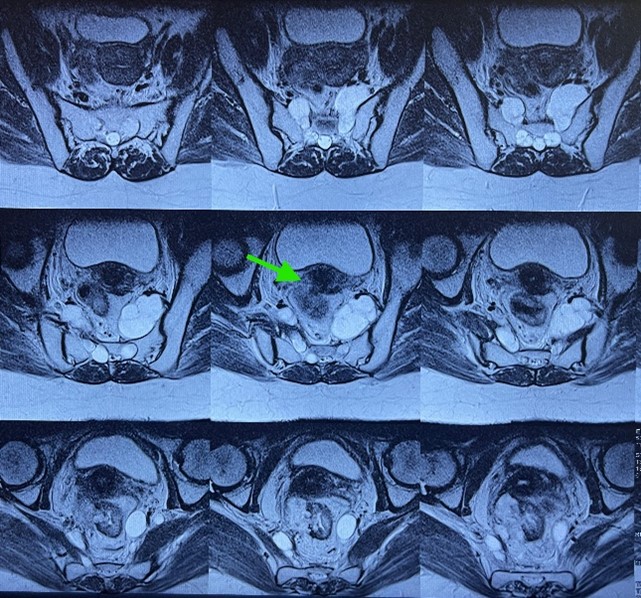

A pelvic MRI demonstrated a tumoral process of the mid and upper rectum, located 55 mm from the anal verge, extending 75 mm in height, infiltrating the right mesorectum with 28 mm of extramural extension, involving the mesorectal fascia, and associated with mesorectal lymph nodes. The tumor was classified as T4aN+Mx.

Figure 1: MRI image showing a tumoral process of the mid and upper rectum, infiltrating the right mesorectum.